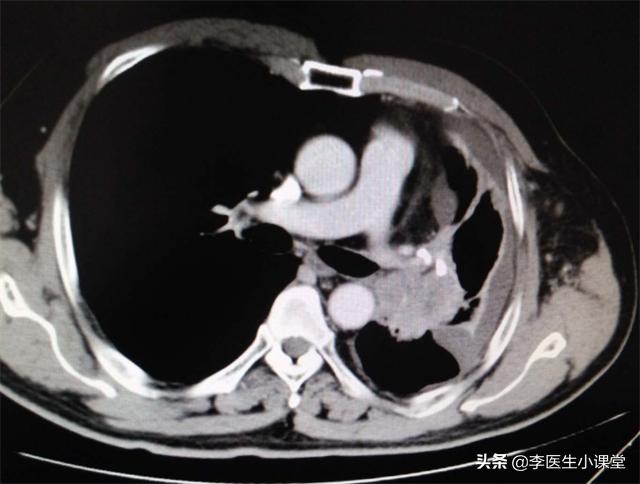

到了医院后,医生给刘先生进行简单的查体,并开了血尿常规和肺部CT的检查,检查结果提示刘先生的肺部出现了大问题。

医生:“ CT显示两肺之间有很多病灶,肺部淋巴结有肿大的迹象,尤其是左上叶的肺部这个病灶,不排除是肿瘤, 我建议你再查一个电子支气管镜来明确病因。”

患者体温36.7℃、血压128/85、身高179cm、体重72kg。肺部CT提示肺部淋巴结肿大,左上叶肺部存在肿瘤,电子支气管镜提示支气管黏膜慢性炎症伴鳞状上皮化生以及局限性癌变。左肺上叶刷片提示存在癌细胞,病理活检显示肺癌晚期。